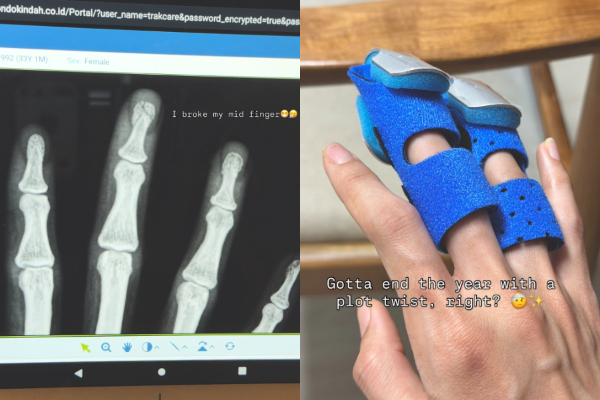

Sabrina Chairunnisa kemudian memperlihatkan hasil rontgen yang menunjukkan adanya keretakan pada bagian ujung atas jari tengahnya. Ia mengungkapkan kondisi tersebut secara blak-blakan.

“I broke my mid finger,” ujar Sabrina.

“Gotta end the year with a plot twist, right?” tulisnya.